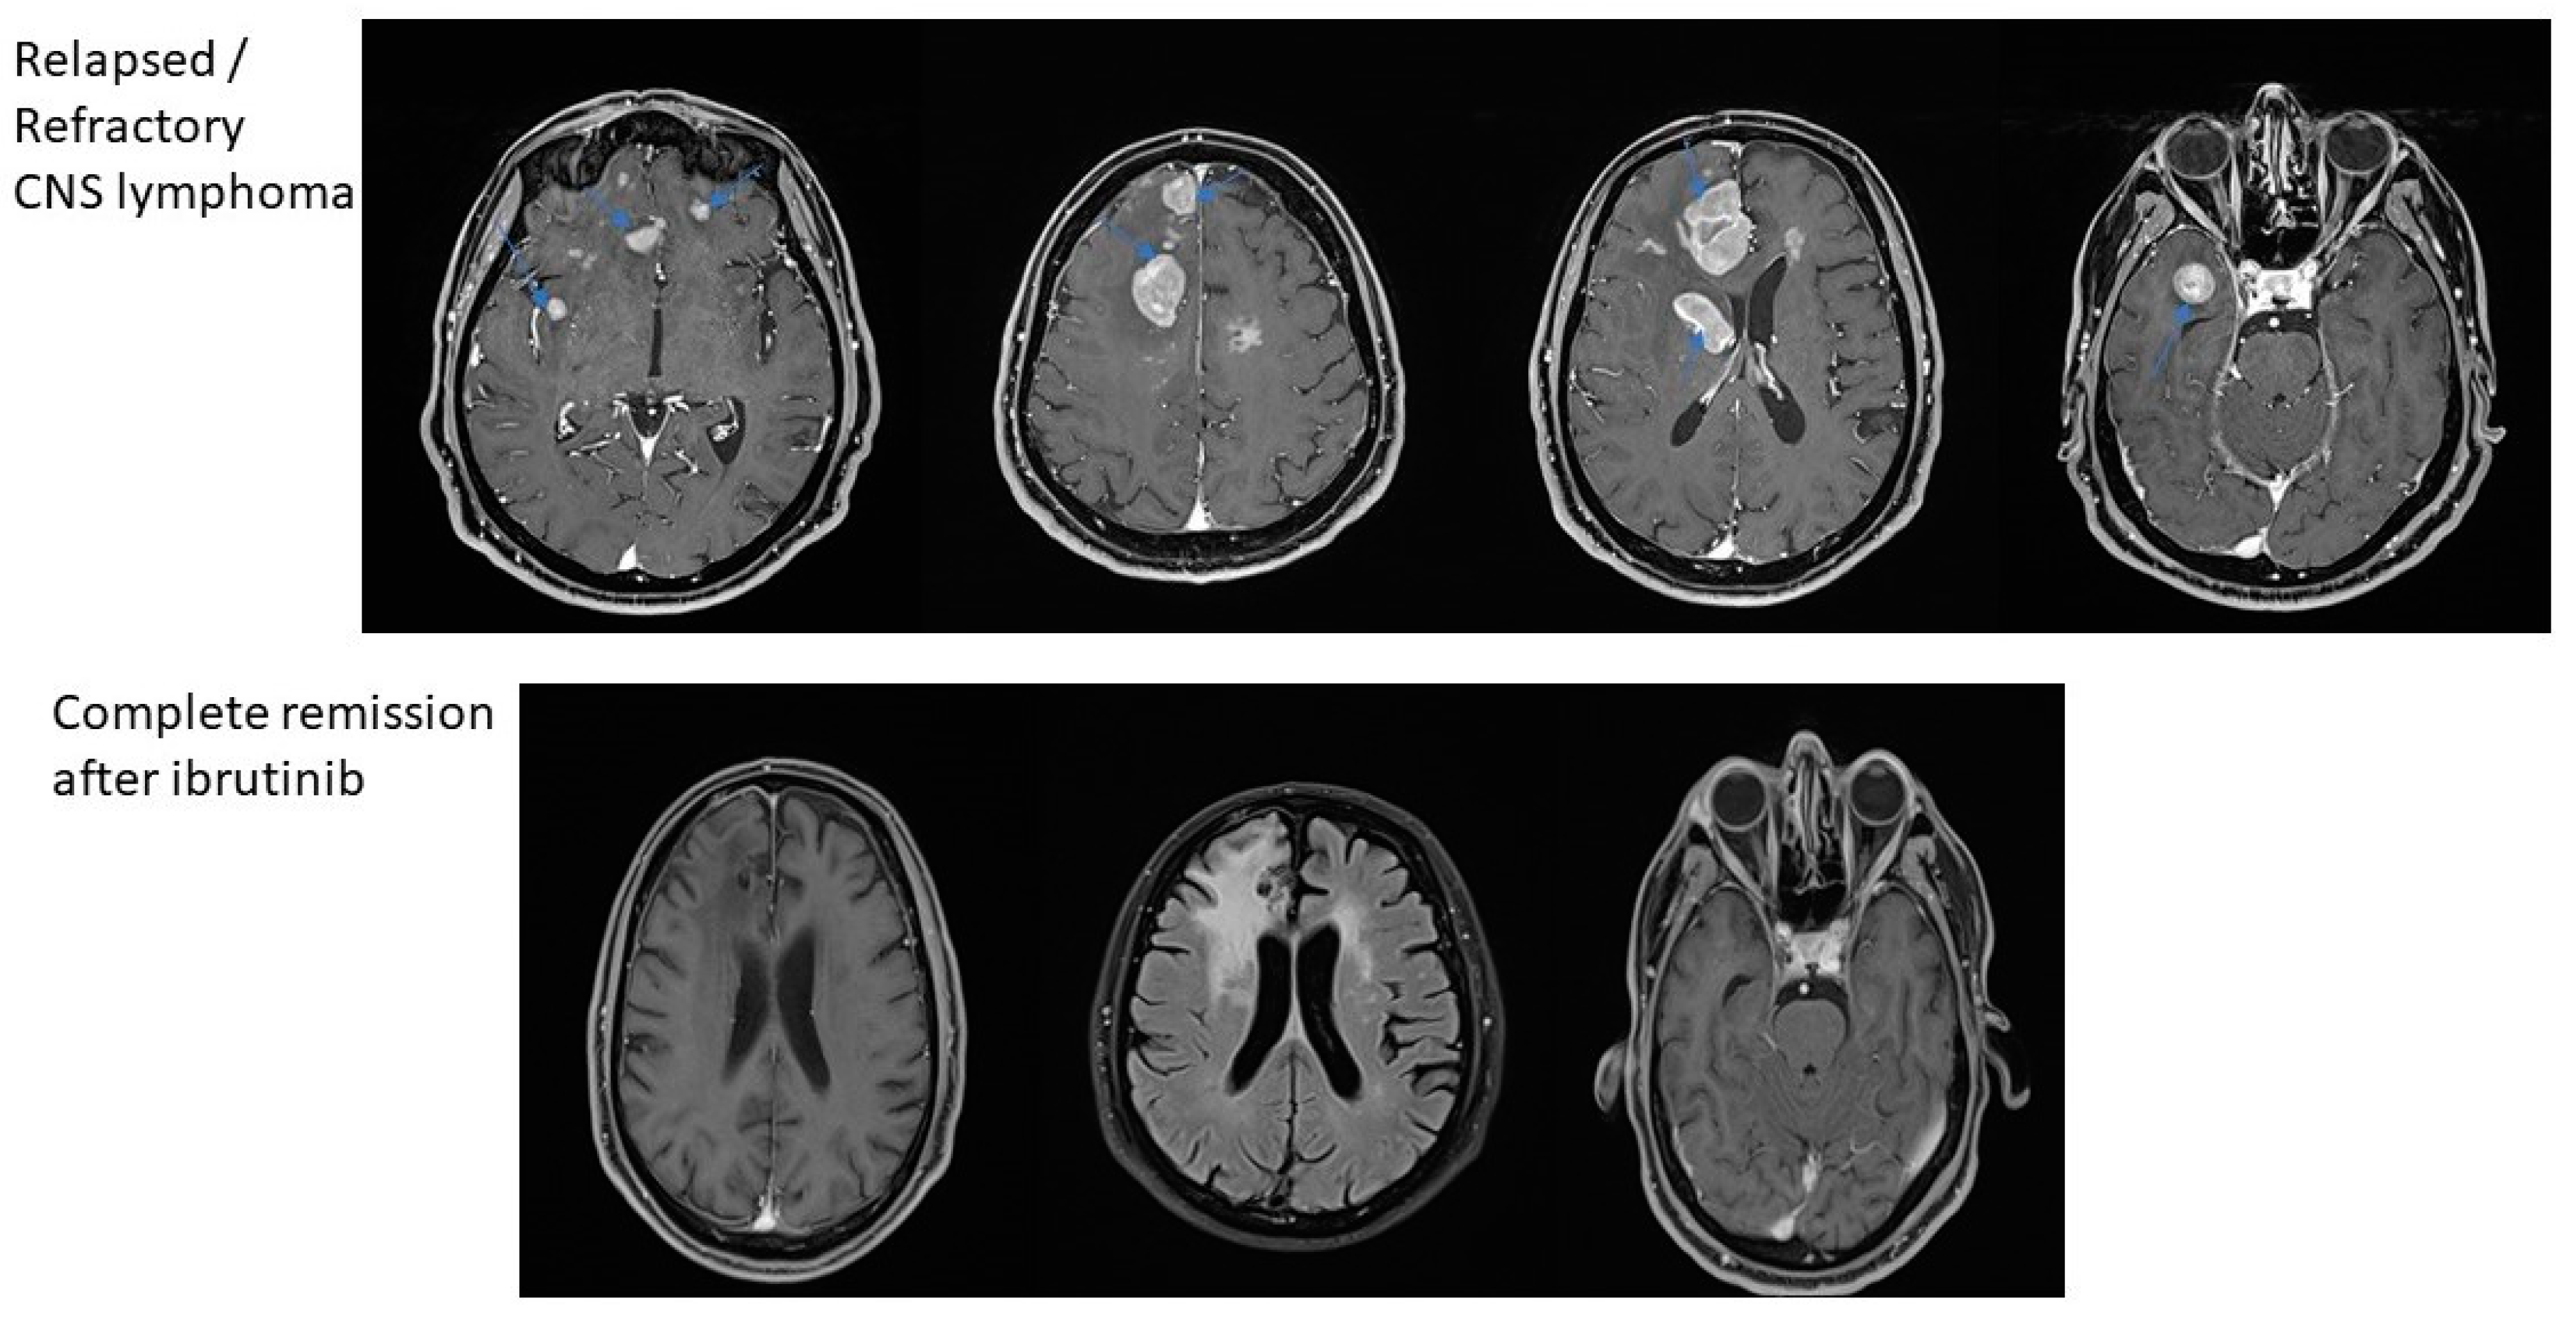

| Case 1 | Complete remission | F | 63 | Right temporal lobe 14/17 mm, right frontal lobe 8 mm, right region of occipital lobe 17/17/22 mm | High-dose methotrexate—5 cycles | Right frontal lobe 7 mm, 2 new lesions: right temporal lobe 10 mm and right parietal lobe 8 mm, without other gadofilic masses | Right frontal lobe 27 mm, right temporal lobe 10 mm, new lesion in right temporal lobe 14 mm. | Ibrutinib monotherapy | No visible lesion | No visible lesion |

| Case 2 | Complete remission | F | 53 | Left frontal lobe 70/40/30 mm | High-dose methotrexate and systemic Rituximab—6 cycles | Stationary disease | Left frontal lobe 50/30/20 mm. | Ibrutinib monotherapy | Left frontal lobe 32.6 mm metabolically inactve | No visible lesion |

| Case 3 | Refractory | M | 64 | Bilateral and insular frontal lobe, superior right frontal region, right basal nuclei and right temporal lobe | High-dose methotrexate—6 cycles | Stationary disease | No lesions at MRI scan. | R-ICE 6 cycles, then second remission was achieved, but after 1 month second relapse: right frontal lobe lesion 20/30 mm. Ibrutinib monotherapy as 3rd line treatment  | Stationary disease | Stationary disease |